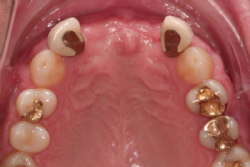

Ein 53jähriger männlicher Patient verlor die beiden Zähne 11 und 21 durch eine Kombination parodontaler und endodontaler Probleme. Nach Abheilung der Extraktionswunden wies der Kieferkamm ein mäßiges vertikales und horizontales Defizit auf.

Abbildung 1: Ästhetisch unbefriedigende Situation nach Entfernung der oberen zentralen Schneidezähne